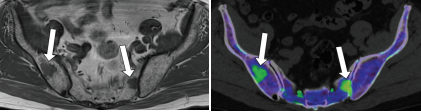

评估骨髓浸润活性